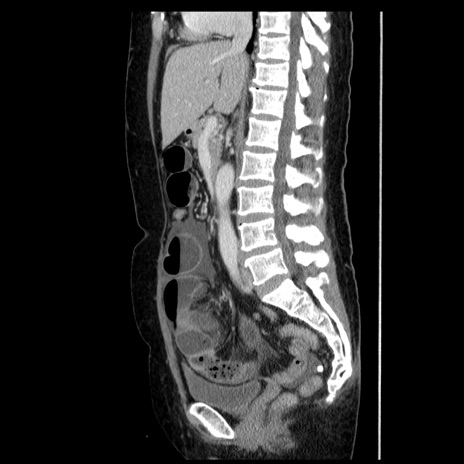

症例6(矢状断像)